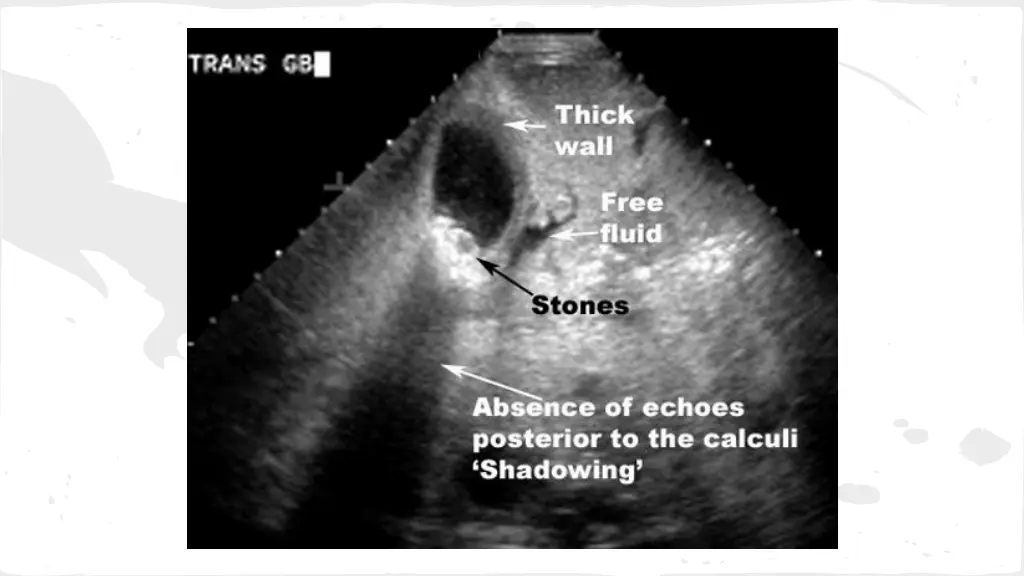

DDX Cholecystitis Cholangitis Hepatitis Pancreatitis Gastritis Pyelonephritis Perforated Ulcer

Findings Symptoms for 10 hours, began after eating Exam: - RUQ TTP - +Murphy's sign Labs: -WBC 14, Lipase nml, lactate 2.4, Alk Phos-274 -AST 224 ALT 198